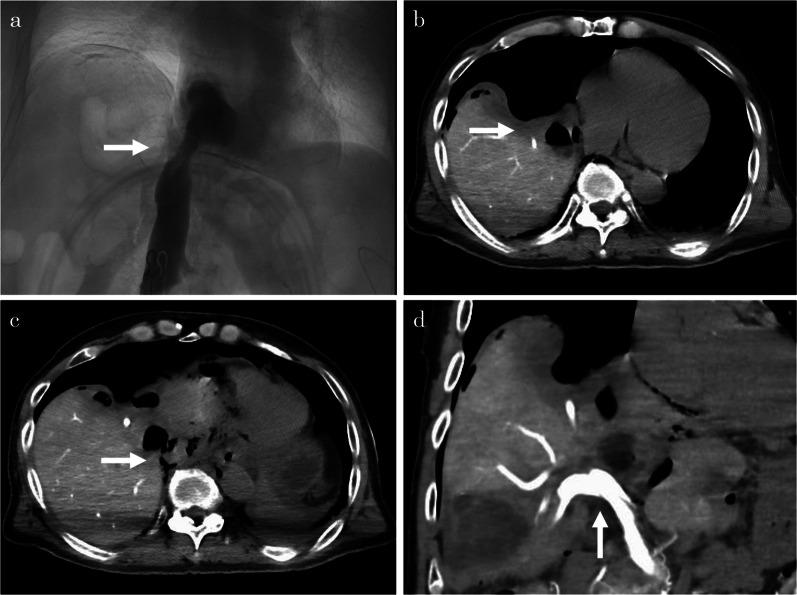

A 73-year-old male presented to a previous doctor with leg edema and dyspnea on exertion; computed tomography revealed that the cause complaint was right lung and heart compression and inferior vena cava (IVC) stenosis due to huge liver cysts in the caudal lobe. The patient was referred to our hospital because of disease recurrence despite percutaneous aspiration of the cyst. Multiple liver cysts were observed in addition to the drained cysts, two of which were located on both sides of the IVC and caused IVC stenosis. We performed open surgery for the liver cysts and used the hybrid operating room for intraoperative IVC angiography and measuring the hepatic vein and portal vein (PV) pressure. We performed unroofing of the hepatic cyst and cauterization of the cyst wall on the hepatic side. Angiography was performed before and after unroofing of the liver cysts, and IVC stenosis release was confirmed. IVC pressure measured at the peripheral side of the stenosis and PV pressures were continuously measured during surgery and were confirmed to have decreased during the opening of the liver cysts. The patient had a good postoperative course and was discharged on the 10th postoperative day. No recurrence was observed 6 months postoperatively.

一名73岁男性因腿部水肿和劳力性呼吸困难就诊于前一位医生;计算机断层扫描显示,病因是尾叶巨大肝囊肿导致右肺和心脏受压以及下腔静脉(IVC)狭窄。尽管对囊肿进行了经皮穿刺抽吸,但由于疾病复发,该患者被转诊至我院。除了已引流的囊肿外,还观察到多发肝囊肿,其中两个位于IVC两侧并导致IVC狭窄。我们对肝囊肿实施了开放手术,并在杂交手术室进行术中IVC血管造影以及测量肝静脉和门静脉(PV)压力。我们对肝囊肿进行去顶术并烧灼肝侧囊肿壁。在肝囊肿去顶术前后进行血管造影,并确认IVC狭窄解除。在狭窄外周侧测量IVC压力,并在手术过程中持续测量PV压力,且在肝囊肿开放期间确认压力下降。患者术后恢复良好,术后第10天出院。术后6个月未观察到复发。